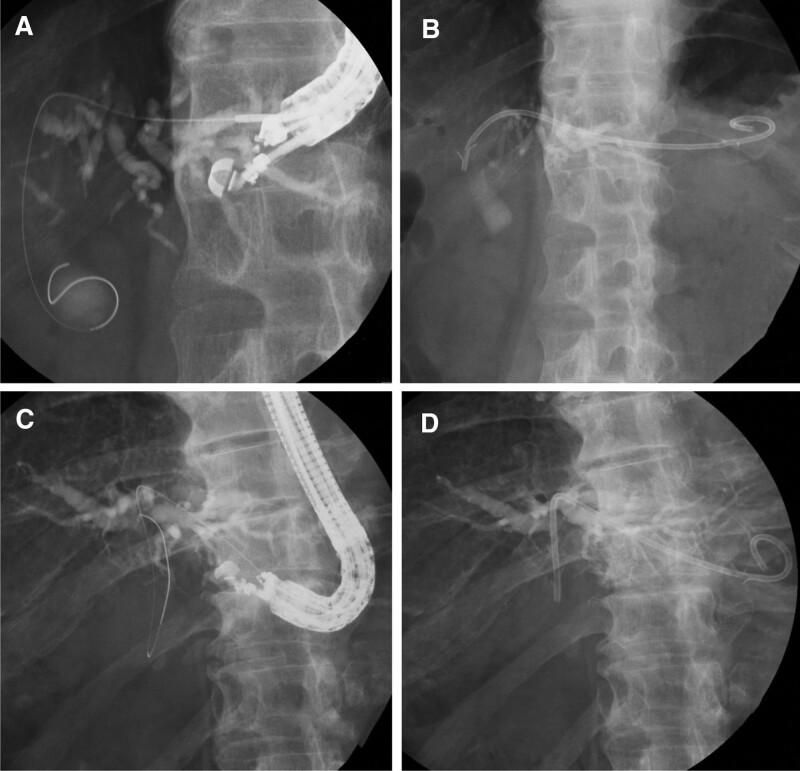

This study aimed to evaluate the feasibility of performing endoscopic ultrasound-guided hepaticogastrostomy using a 22-gauge fine-needle aspiration needle. This was a single-center retrospective study. Fourteen patients who underwent endoscopic ultrasound-guided hepaticogastrostomy with a 22-gauge fine-needle aspiration needle were examined. Fourteen eligible patients were included in this study. The age of patients ranged from 55 to 93 years, with a median of 76 years. Of patients with existing underlying diseases, there were 8 cases of pancreatic cancer (57.1%), 2 cases of metastatic liver tumor (14.3%), 2 cases of bile duct stones (14.3%), 1 case of hilar cholangiocarcinoma (7.1%), and 1 case of gallbladder cancer (7.1%). Regarding gastrointestinal anatomy, there were 11 cases (78.6%) of normal and 3 cases (21.4%) of gastric resection with Roux-en-Y. Reasons for endoscopic ultrasound-guided hepaticogastrostomy were duodenal obstruction in 7 cases (50.0%), surgically altered anatomy in 3 cases (21.4%), and 4 cases (28.6%) of failed endoscopic retrograde cholangiopancreatography. Technical success was achieved in 11 cases (78.6%). Subsequently, 11 cases of technical success were analyzed. There were 5 cases of puncturing B2 (45.5%). The puncture bile duct diameter ranged from 3.1 to 5.7 mm, with a median of 4.4 mm. endoscopic ultrasound-guided antegrade procedures was combined with endoscopic ultrasound-guided hepaticogastrostomy in 2 cases (18.2%). Clinical success was achieved in all the cases. The procedure time ranged from 15 to 93 minutes, with a median duration of 35 minutes. Regarding the type of stent placed in hepaticogastrostomy, a plastic stent was placed in 10 cases (90.9%) and a metal stent was placed in 1 case (9.1%). Early adverse events occurred in 4 cases (36.4%), and all of these cases developed biliary peritonitis, late adverse events occurred in 1 case (9.1%), this was biloma. A change to a 0.025-inch guidewire during the procedure was required in 8 cases (72.7%). Esophageal puncture was not performed. endoscopic ultrasound-guided hepaticogastrostomy using a 22-gauge fine-needle aspiration needle is effective. However, in 72.7% of the cases started using the 0.018-inch guidewire, the guidewire was exchanged for a 0.025-inch guidewire during procedure.